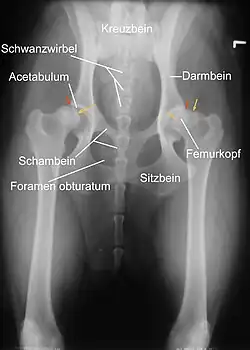

Eine zuverlässige Möglichkeit, den Schweregrad der Erkrankung zu erkennen, ist die Röntgenuntersuchung. Dabei müssen die Gelenke überstreckt werden, was beim Vorliegen einer HD starke Schmerzen verursacht. Daher wird sie unter Kurznarkose durchgeführt. Voraussetzung für eine aussagekräftige Diagnose ist die exakte Positionierung des Tieres in Rückenlage mit gestreckten, parallel gelagerten Oberschenkeln und rechtwinklig zum Strahlengang eingedrehten Kniescheiben. Die ordnungsgemäße Lagerung kann anhand der Form der Foramina obturatoria, der Form der Darmbeinschaufeln, der Breite der Darmbeinsäulen und der Position der Kniescheiben beurteilt werden. Zusätzliche Aufnahmen können in „Froschhaltung“ der Oberschenkel oder im seitlichen (latero-lateralen) Strahlengang erfolgen, in Deutschland wird dies nur bei Obergutachten durchgeführt.[3]

Man unterscheidet bei der Beurteilung primäre Kriterien wie die Ausformung des Hüftgelenks und Feststellung einer Inkongruenz, der Grad der Lockerheit des Gelenks und die Ausformung der Gelenkpfanne und des Hüfkopfes sowie sekundäre Kriterien, welche auf eine Arthrose hinweisen.[3]